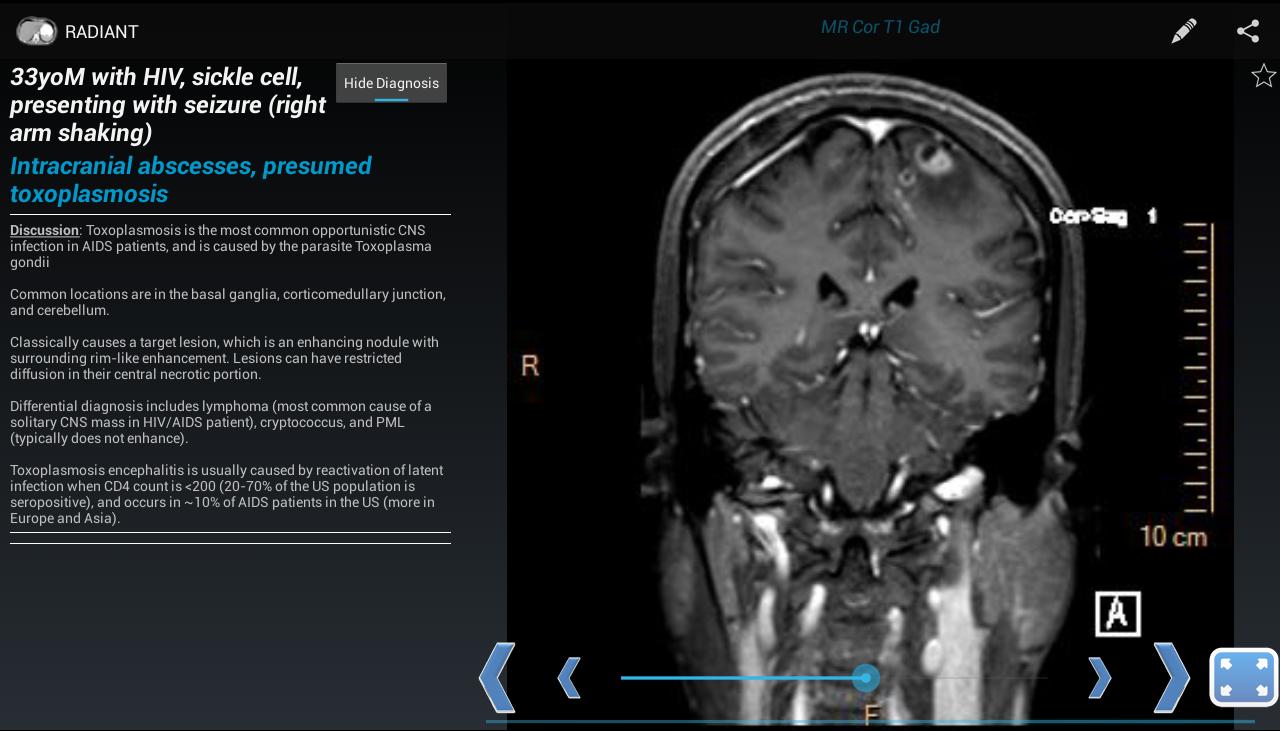

Radiantは、主に医療分野のユーザー向けの画像ベースの教育資料を作成、管理、共有するプラットフォームです。診断放射線科の住民、仲間、医学生、教員の間で興味深いケースを共有するのに最適です。診断に使用することを意図したものではありません。

コンテンツは、基本コンポーネントとして単一の画像を中心に編成されています。複数の関連画像では、画像スタックをスクロールできるシリーズで構成されています。これらの画像シリーズは、ケースのビルディングブロック(1人の特定の患者の特定の診断の画像所見を示す関連シリーズ)、ファイル(テキストブックのような章や章で編成されたトピック)、およびテスト(関連する画像シリーズとのリンクされた質問)を形成します。ケースはケースパックにグループ化できます。ケースパックでは、作成するのに数秒しかかかりません。最後の不明なケースプレゼンテーションや集中的な勉強に最適です。

放射を使用すると、X線、超音波、CT、MRI、またはその他のイメージングモダリティを示すケースを作成できます。これは、実際の高品質の診断医療画像を使用して、胸部X線、正常な解剖学、および一般的な疾患プロセスを学ぶのに最適な方法です。